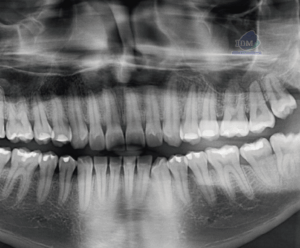

CARACTERISTICAS RADIOGRÁFICAS

La enfermedad de Paget ocurre con más frecuencia en la pelvis, fémur, cráneo y vértebras y en raras ocasiones en los maxilares. Afecta con mayor frecuencia al maxilar superior. Aunque la enfermedad es bilateral puede existir un solo maxilar afectado. La estructura interna se puede observar en tres estadios, el primero radiolúcido, un segundo estadio granular y el tercero se observa como un estadio aposicional tardío más denso y radiopaco. Las trabéculas suelen estar alteradas en cuanto al número y la forma. La densidad media de los maxilares puede disminuir o aumentar dependiendo del número de trabéculas.

Fig 1. Radiografía oclusal lateral que muestran osteosclerosis y un aspecto de copos de algodón.